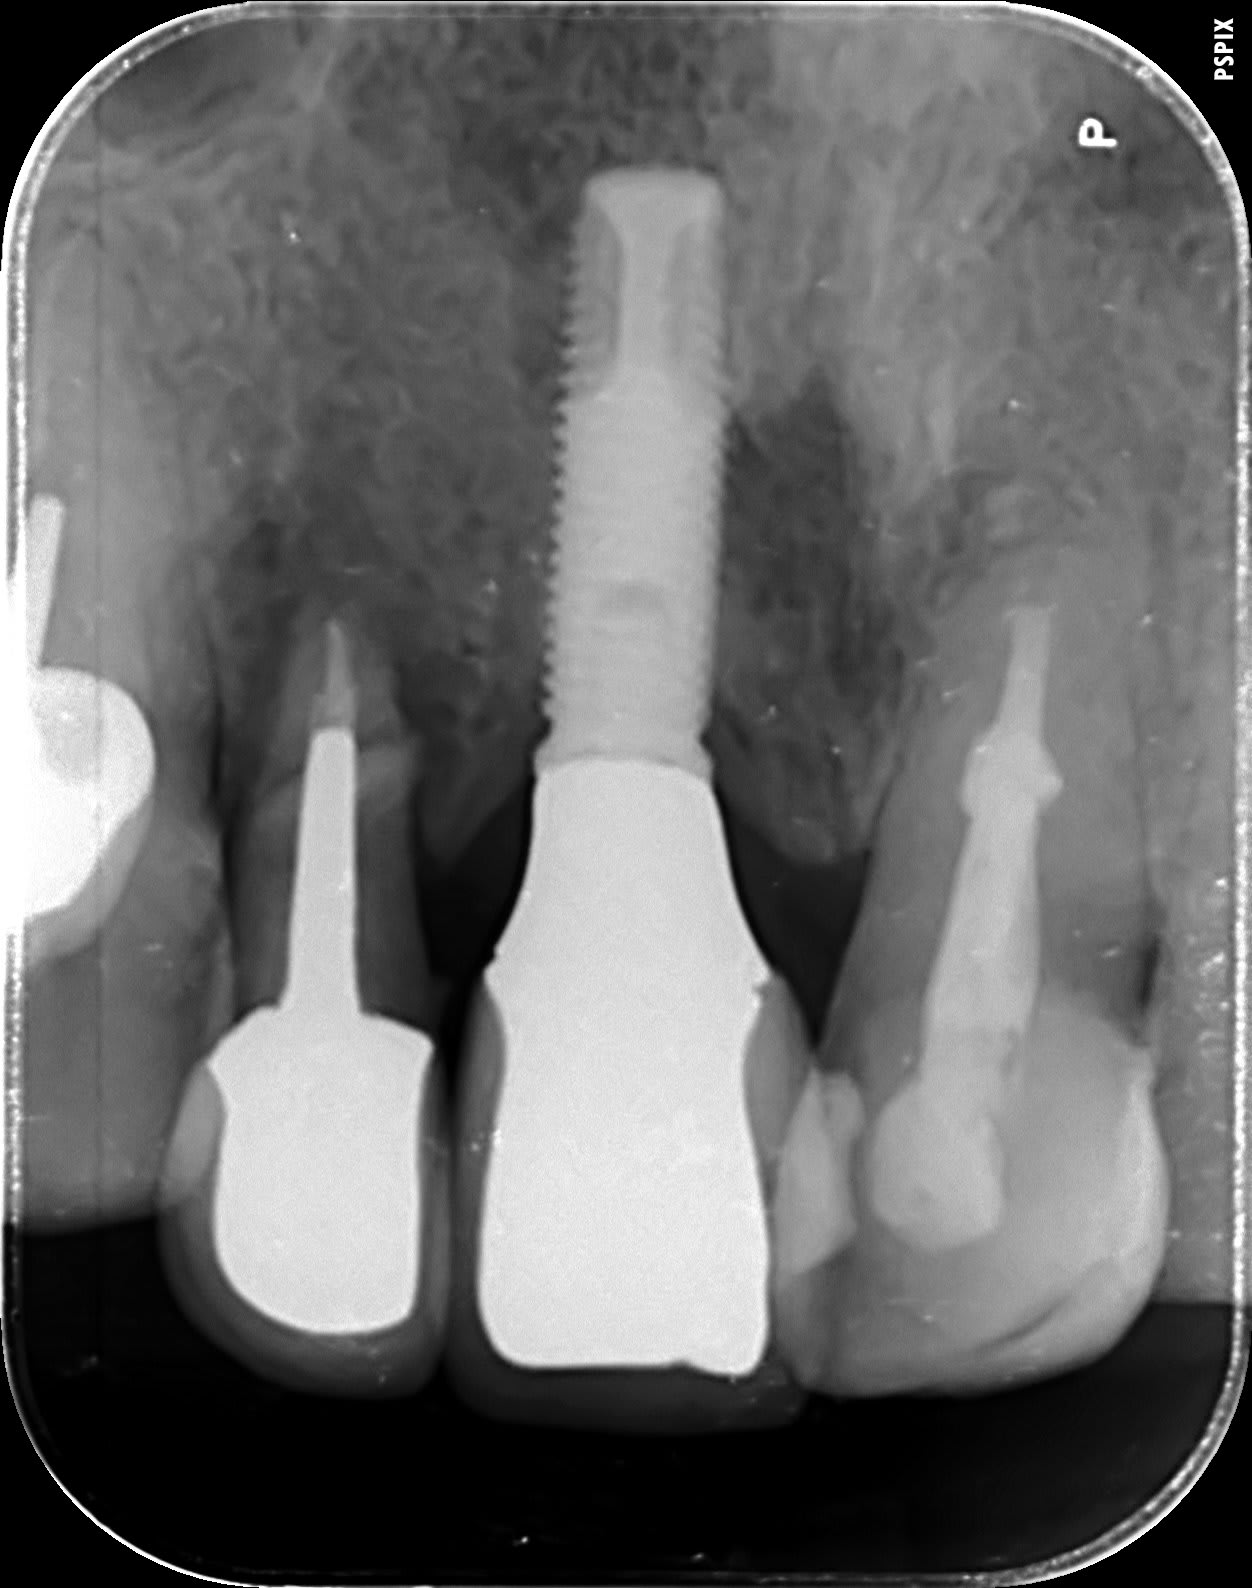

bein oui, mais là tu me reprends une radio bien nette avec l'apex bien visible parce que là je dois avoir 150 possibilités même si j'ai ma petite idée...

Nobel MK3 ou 3i connectique hexagone externe?

Implant pose il y a 20ans

je dirais un 3I 4 de diametre

non, avec cette forme de lames de coupe apicale perso un Nobel mk3 çà m'inspire plus...

maintenant c'est vrai que c'est proche de la forme d'un 3i et que pour être certain...faut voir la totalité de l'apex de cet implant...

=> nouvelle radio stp!!!

Tiens Pluton.. alors Nobel? merci

yes, c'est un Nobel...mk2 ou Mk3 (plus certainement mk3), mais peu importe, c'est la même connexion externe...;-)

Un beau cas pour un bridge implantaire avec pilier central et cantilever bilatéral

Même tourne cis que pour du Nobel actuel? Unigrip?

La 21 je comptais La garder.. aucune mobilité malgré la ryzalyze. Sondage pk.

La 12 va dégager en revanche au profit d'un cantilever.

Beau résultat implantaire en tout ca!!